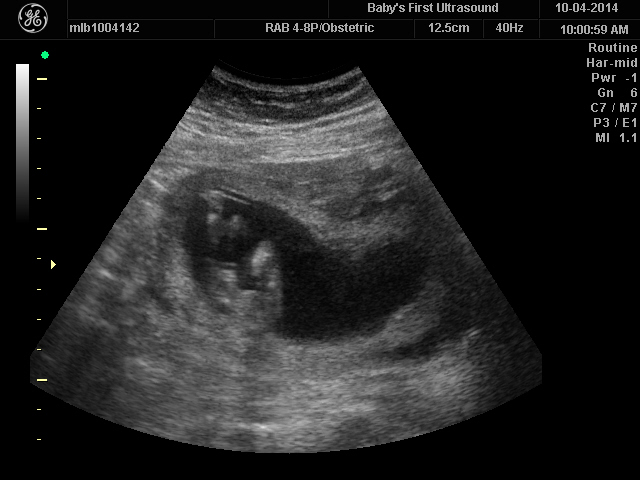

Attachment 21524Attachment 21525

I'd lean girl I think GL

Not seeing much so leaning girl too

Girl

Looking pink.

Thinking pink!

Gurl Sent from my iPhone using Tapatalk